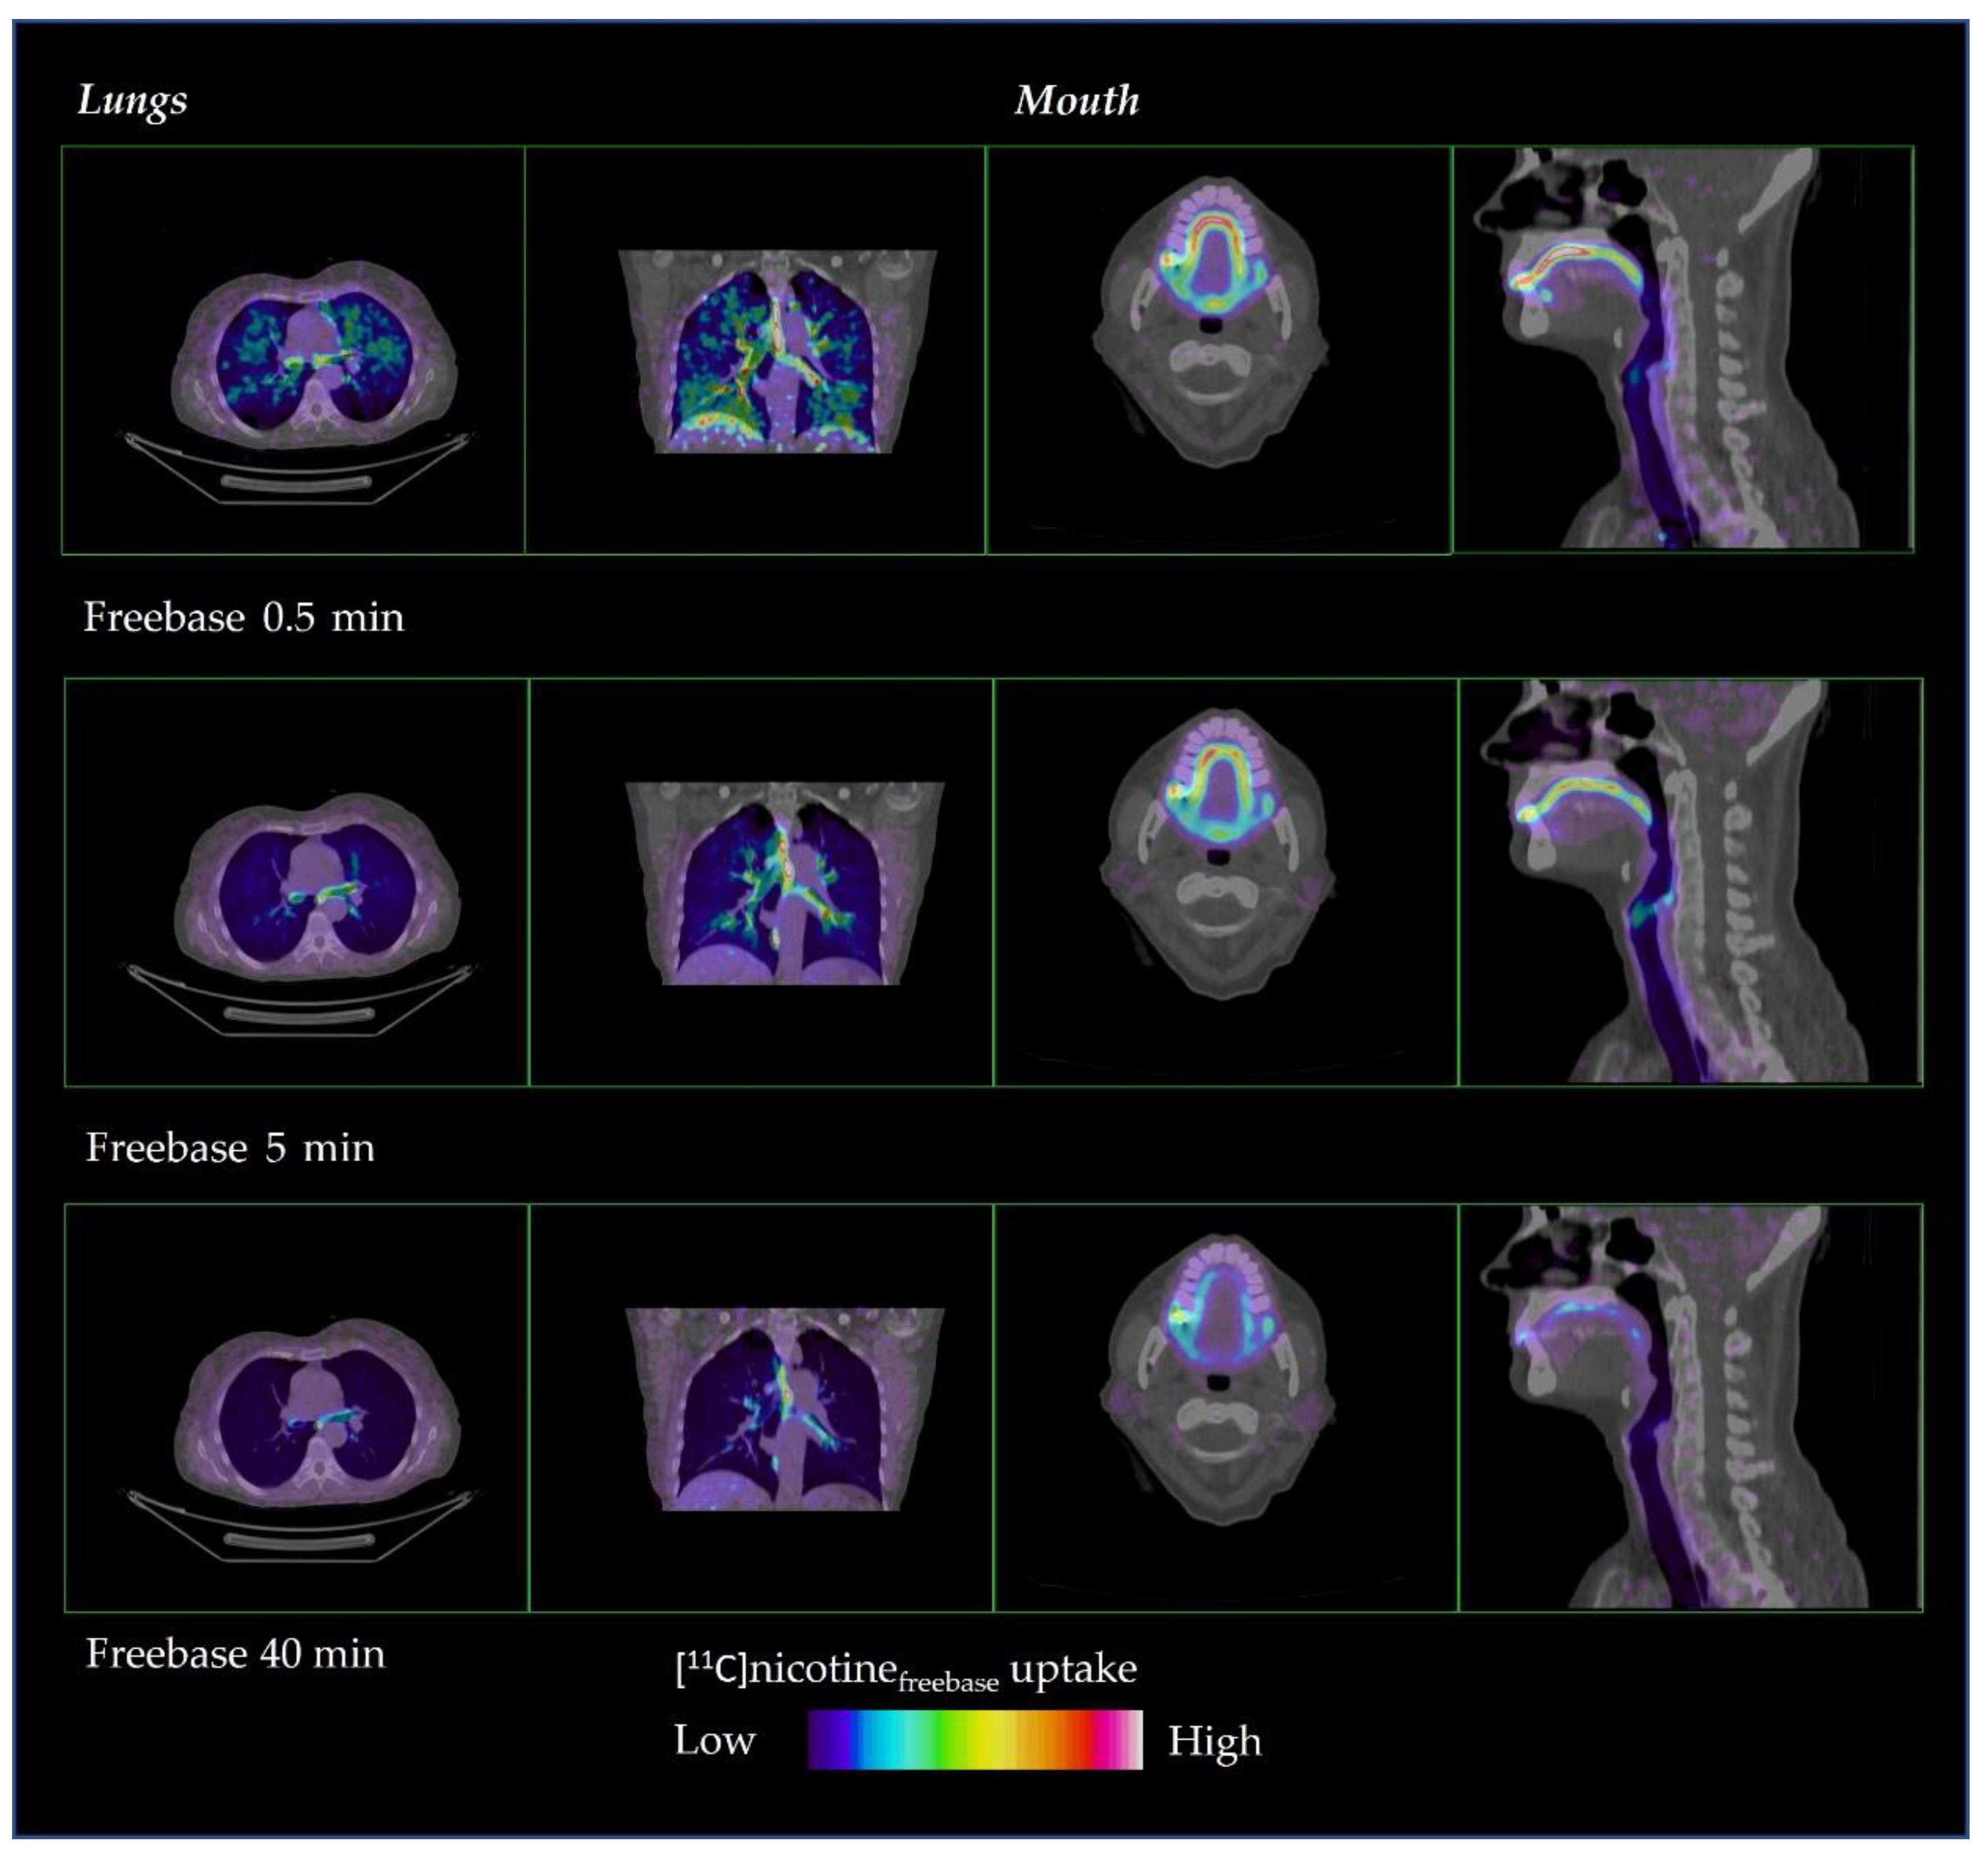

The distribution of [11C]nicotine over time is shown in Figure 2 and Figure 3 for freebase nicotine and nicotine lactate formulations, respectively. The same subjects are considered as in Figure 1.

Figure 2.

Representative distribution of [11C]nicotinefreebase in lungs and mouth at 0.5, 5 and 40 min after inhalation.

[11C]Nicotinefreebase had a fast distribution through the oral cavity, upper respiratory pathways and the lung parenchyma (Figure 2). However, the freebase [11C]nicotine tended to remain in the oral cavity and upper respiratory pathways during the entire PET scan, up to 40 min.